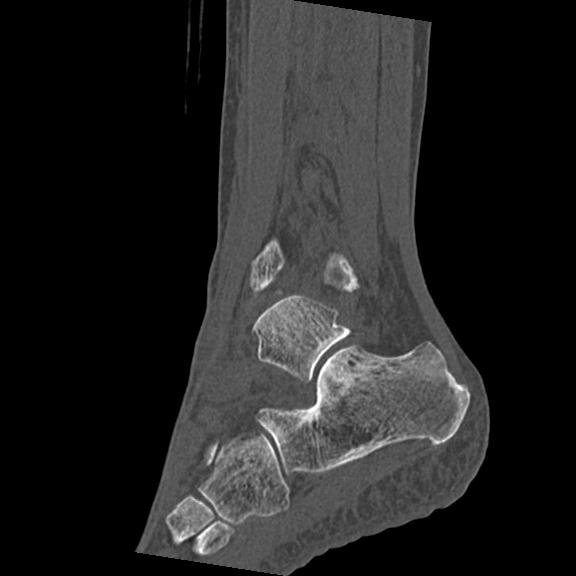

56476 8/28 4R 1/21 2R 左足関節 デジカメ写真 72歳女性 右足関節AS

102755 1/4 2R 1/15 2R 右足関節 68歳女性 右三果脱臼骨折